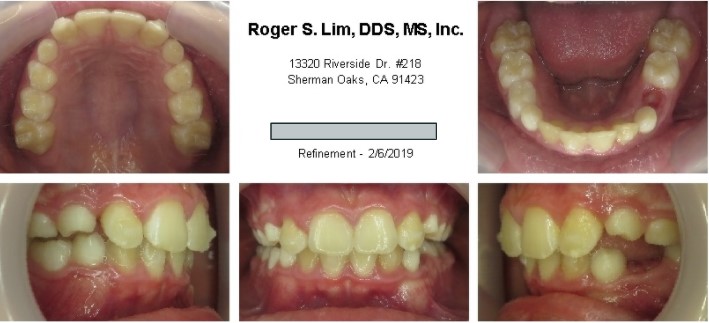

Posterior crossbite before Expander

Posterior crossbite after Expander